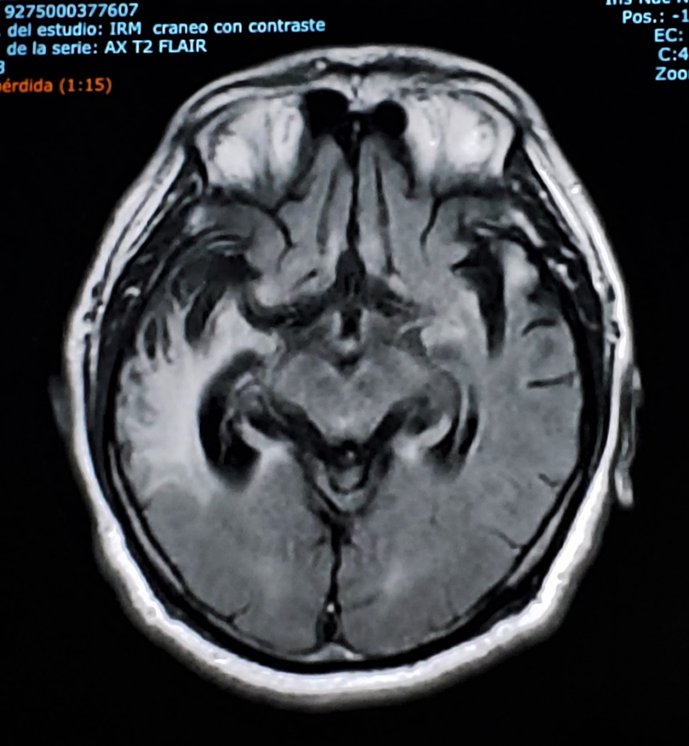

A 25 year old man comes to the emergency room with an acute history of hallucinations, persecutory delusions, aggresive behavior, psychomotor agitation. The mental status examination shows severe cognitive dysfunction. This is the brain image. Thoughts?

Jesus Ramirez-Bermudez tweet media